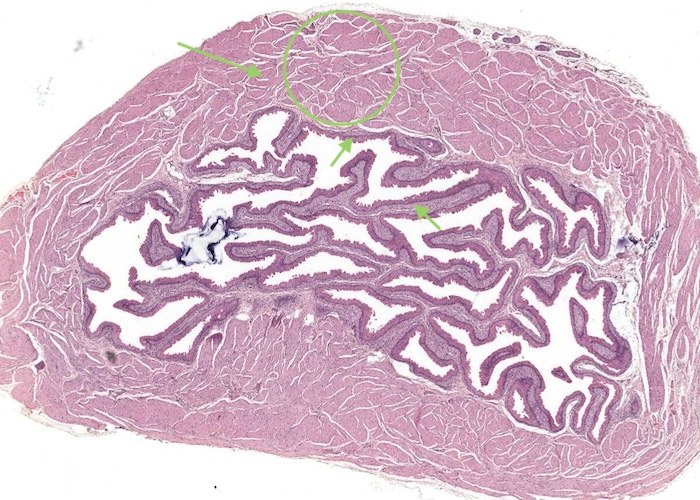

At low magnification, observe the three layers of the ureter: mucosa, muscularis and adventitia. This organization is maintained throughout the urinary passages. The mucosa of the ureter is thrown into characteristic longitudinal folds. It is made of transitional epithelium underlain by a layer of fairly cellular connective tissue (lamina propria). Quite a few lymphocytes are found in this lamina propria. The muscularis layer consists of two somewhat diffuse sheets of smooth muscle: the inner is longitudinal, and the outer is circular. Towards the bladder end it picks up a third oblique layer. This muscle produces peristaltic waves that push the urine to the bladder even when you are lying down. The adventitia is made of connective tissue and contains the nerves and blood vessels that supply the organ. One thing to note is that the ureter runs through loose connective tissue from the kidney to the bladder.

The ureter and also the other passages within the kidney through which urine flows i.e. the calyces and renal pelvis, are lined by transitional epithelium (often referred to as urothelium). The details of the layers of cells within this type of epithelium is best described in the later item "lumenal epithelium" of the bladder but generally it is 2-3 cell layers thick in the minor calyces but much thicker as you see here in the ureter and then the bladder.

Connective tissue and smooth muscle make up the remainder of the wall of the ureter. The smooth muscle is in longitudinal and circular layers so when you examine the section see if you can pick out these longitudinal and circular layers of muscle.